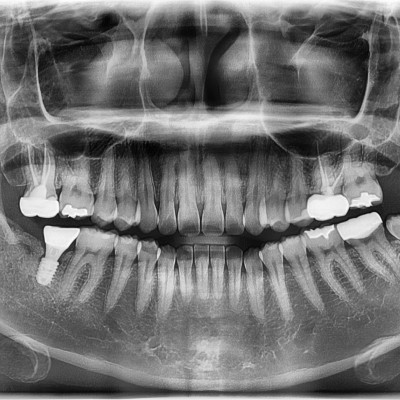

#18,28,48 사랑니 발치 #18,28,48 사랑니 발치 구강 외과 전문의가 당일 발치했습니다.